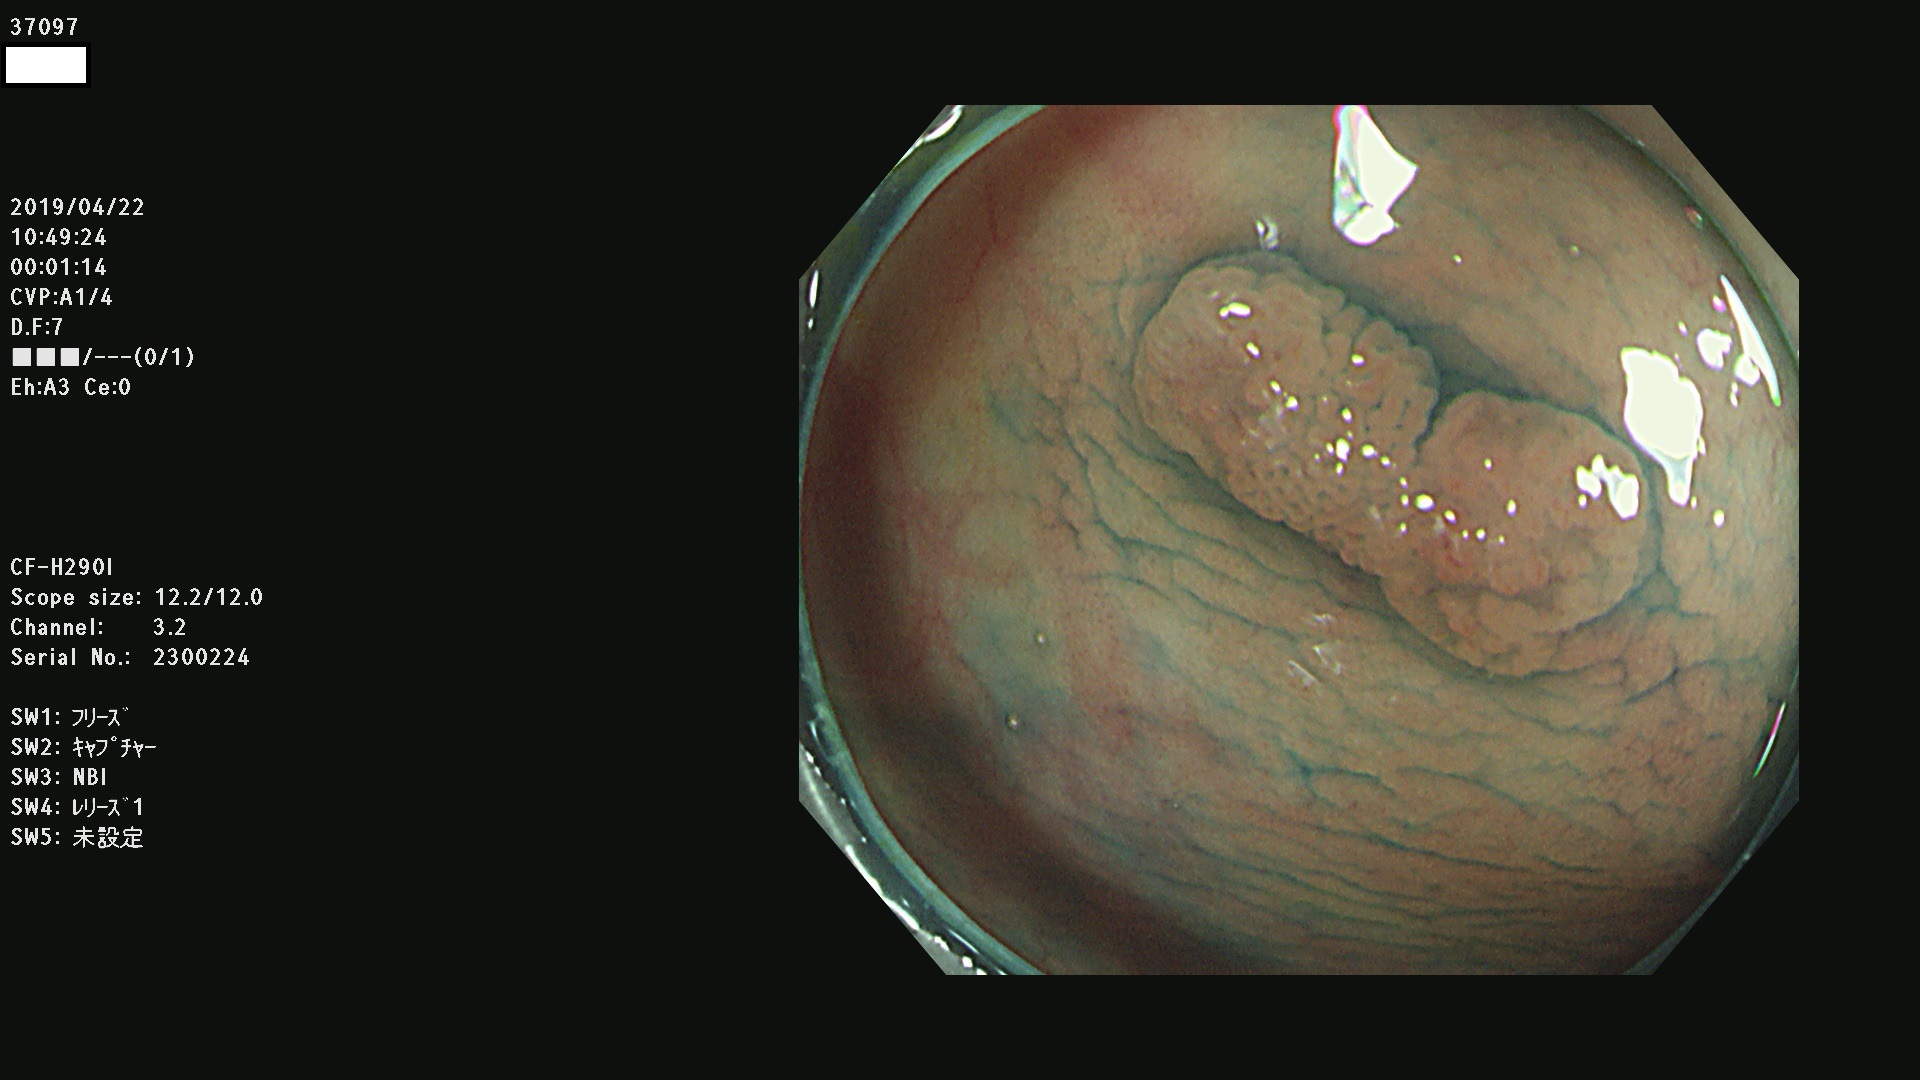

37000 37002 37004 37005 37006(SSAPのみ) 37007 37009 37013 37014 37015 37017(SSAPのみ) 37019 37020 37021 37022 37025 37026 37027 37028 37029 37031 37032 37033 37034 37035 37036 37037 37038 37041 37042 37043 37044 37045 37047 37051 37052 37053(SSAPのみ) 37055 37056 37058 37060 37061 37062 37063 37067 37072 37073 37074 37076 37077 37078 37079 37080 37081 37083 37084 37085(SSAPのみ) 37086 37087 37088 37089 37092 37093 37094 37095 37097 37098 3709

発見困難で危険性の高い平坦型病変(上記100名より抽出)